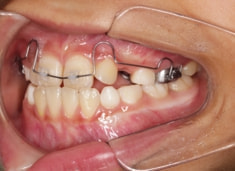

治療法:上顎急速拡大装置+クリアスナップ+フェイスマスク+上顎3番は開窓牽引CT写真にて位置確認

治療開始時

検査時のレントゲン分析では、上下顎の関係は、上顎の劣成長があり下顎前突傾向という値がでておりましたが、前歯ジャンプ後はフェイスマスクの効果もあり、上下顎の関係は正常化しています。

上顎が若干優位になっていますので、今後の下顎の成長のための貯金になっているくらいです。